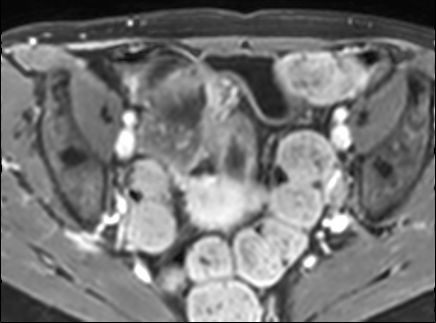

Bệnh nhân nữ 48 tuổi, đang điều trị bằng thuốc kháng TNF, được chỉ định nội soi đại tràng.

Phát hiện hẹp lòng ruột ở đại tràng sigma, không thể vượt qua được khi nội soi.

MR-enterography được thực hiện để đánh giá mức độ lan rộng của chỗ hẹp.

Ruột non bình thường, nhưng ghi nhận các đoạn hẹp ở đại tràng xuống và đại tràng ngang.

Cả hai đoạn hẹp đều có thành ruột dày đến 8 mm và ngấm thuốc rõ rệt theo kiểu niêm mạc ở đại tràng xuống và kiểu phân lớp ở đại tràng ngang.

Giãn ruột trước chỗ hẹp được ghi nhận ở cả hai đoạn.

Do các chỗ hẹp này không hiện diện khi nội soi đại tràng trước khi điều trị kháng TNF, nhiều khả năng chúng đã hình thành trong quá trình điều trị.

Do đó, quyết định phẫu thuật cắt đại tràng gần toàn bộ với miệng nối hồi-sigma đã được đưa ra.